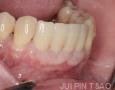

3 Months

13 Months